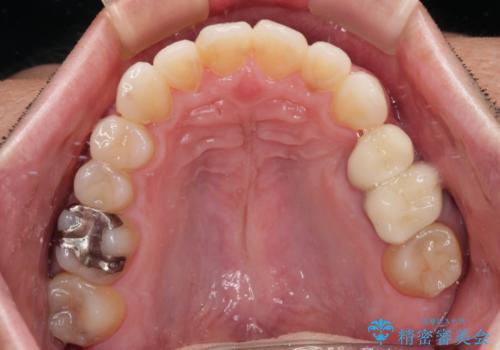

内側に転位した歯とボロボロのむし歯 インビザラインによる矯正治療とむし歯治療

矯正治療後には抜歯が必要な歯に隣接してむし歯となっていた歯をオールセラミッククラウンにて補綴治療を行うこととしました。

矯正治療開始時に、インビザライン矯正の加速装置を購入されましたが、インビザライン自体をあまりしっかりと使用できず、4年間の治療期間となりました。